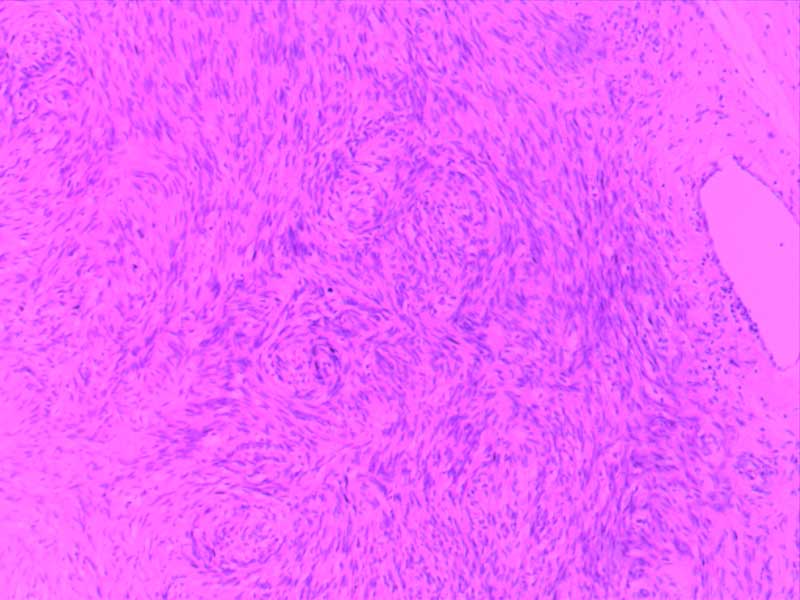

纤维肉瘤10-倍